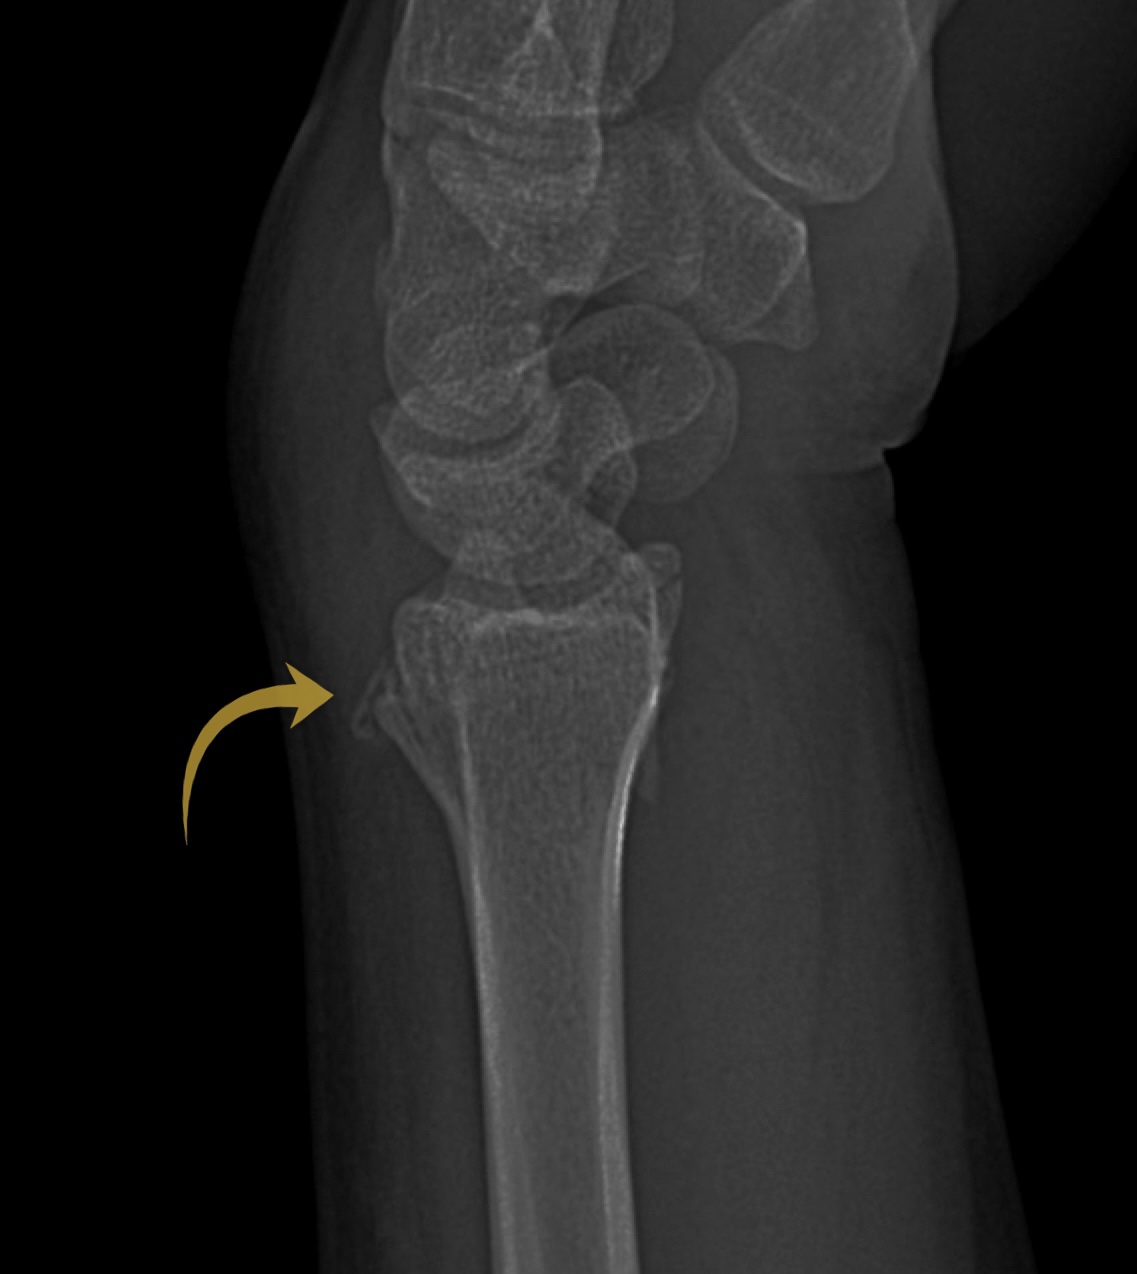

Case 9

A female in their 70s presents with wrist pain after a fall onto an outstretched hand (FOOSH). Assess the following wrist X-Ray. What is the most likely diagnosis?

Choose from one of the following options: